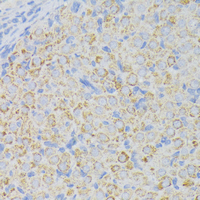

Immunohistochemical analysis of ACADL staining in rat ovary formalin fixed paraffin embedded tissue section. The section was pre-treated using heat mediated antigen retrieval with sodium citrate buffer (pH 6.0). The section was then incubated with the antibody at room temperature and detected using an HRP conjugated compact polymer system. DAB was used as the chromogen. The section was then counterstained with haematoxylin and mounted with DPX.